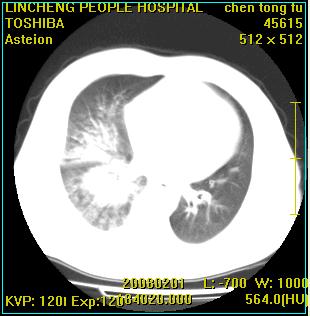

标题: CT11942:男性,62岁。右肺的病变 [打印本页]

患者,男性,62岁。主因头晕,发热,咳嗽6天,高热达39度,esr19mm/h,wbc 3.9×10 9/l

实变区见空气支气管征,支气管通畅,考虑为大叶性肺炎,右侧少量胸水

考虑为右肺大叶性肺炎伴少量胸腔积液,建议复查,如病变不吸收或吸收不明显,建议纤维支气管镜检查,除外细支气管肺泡癌的可能。

请教各位,大叶性肺炎可以每个叶都有吗?不是多数发生在一个叶吗?跨叶的多吗?

实变区见空气支气管征,支气管通畅,考虑为大叶性肺炎,右侧少量胸水。